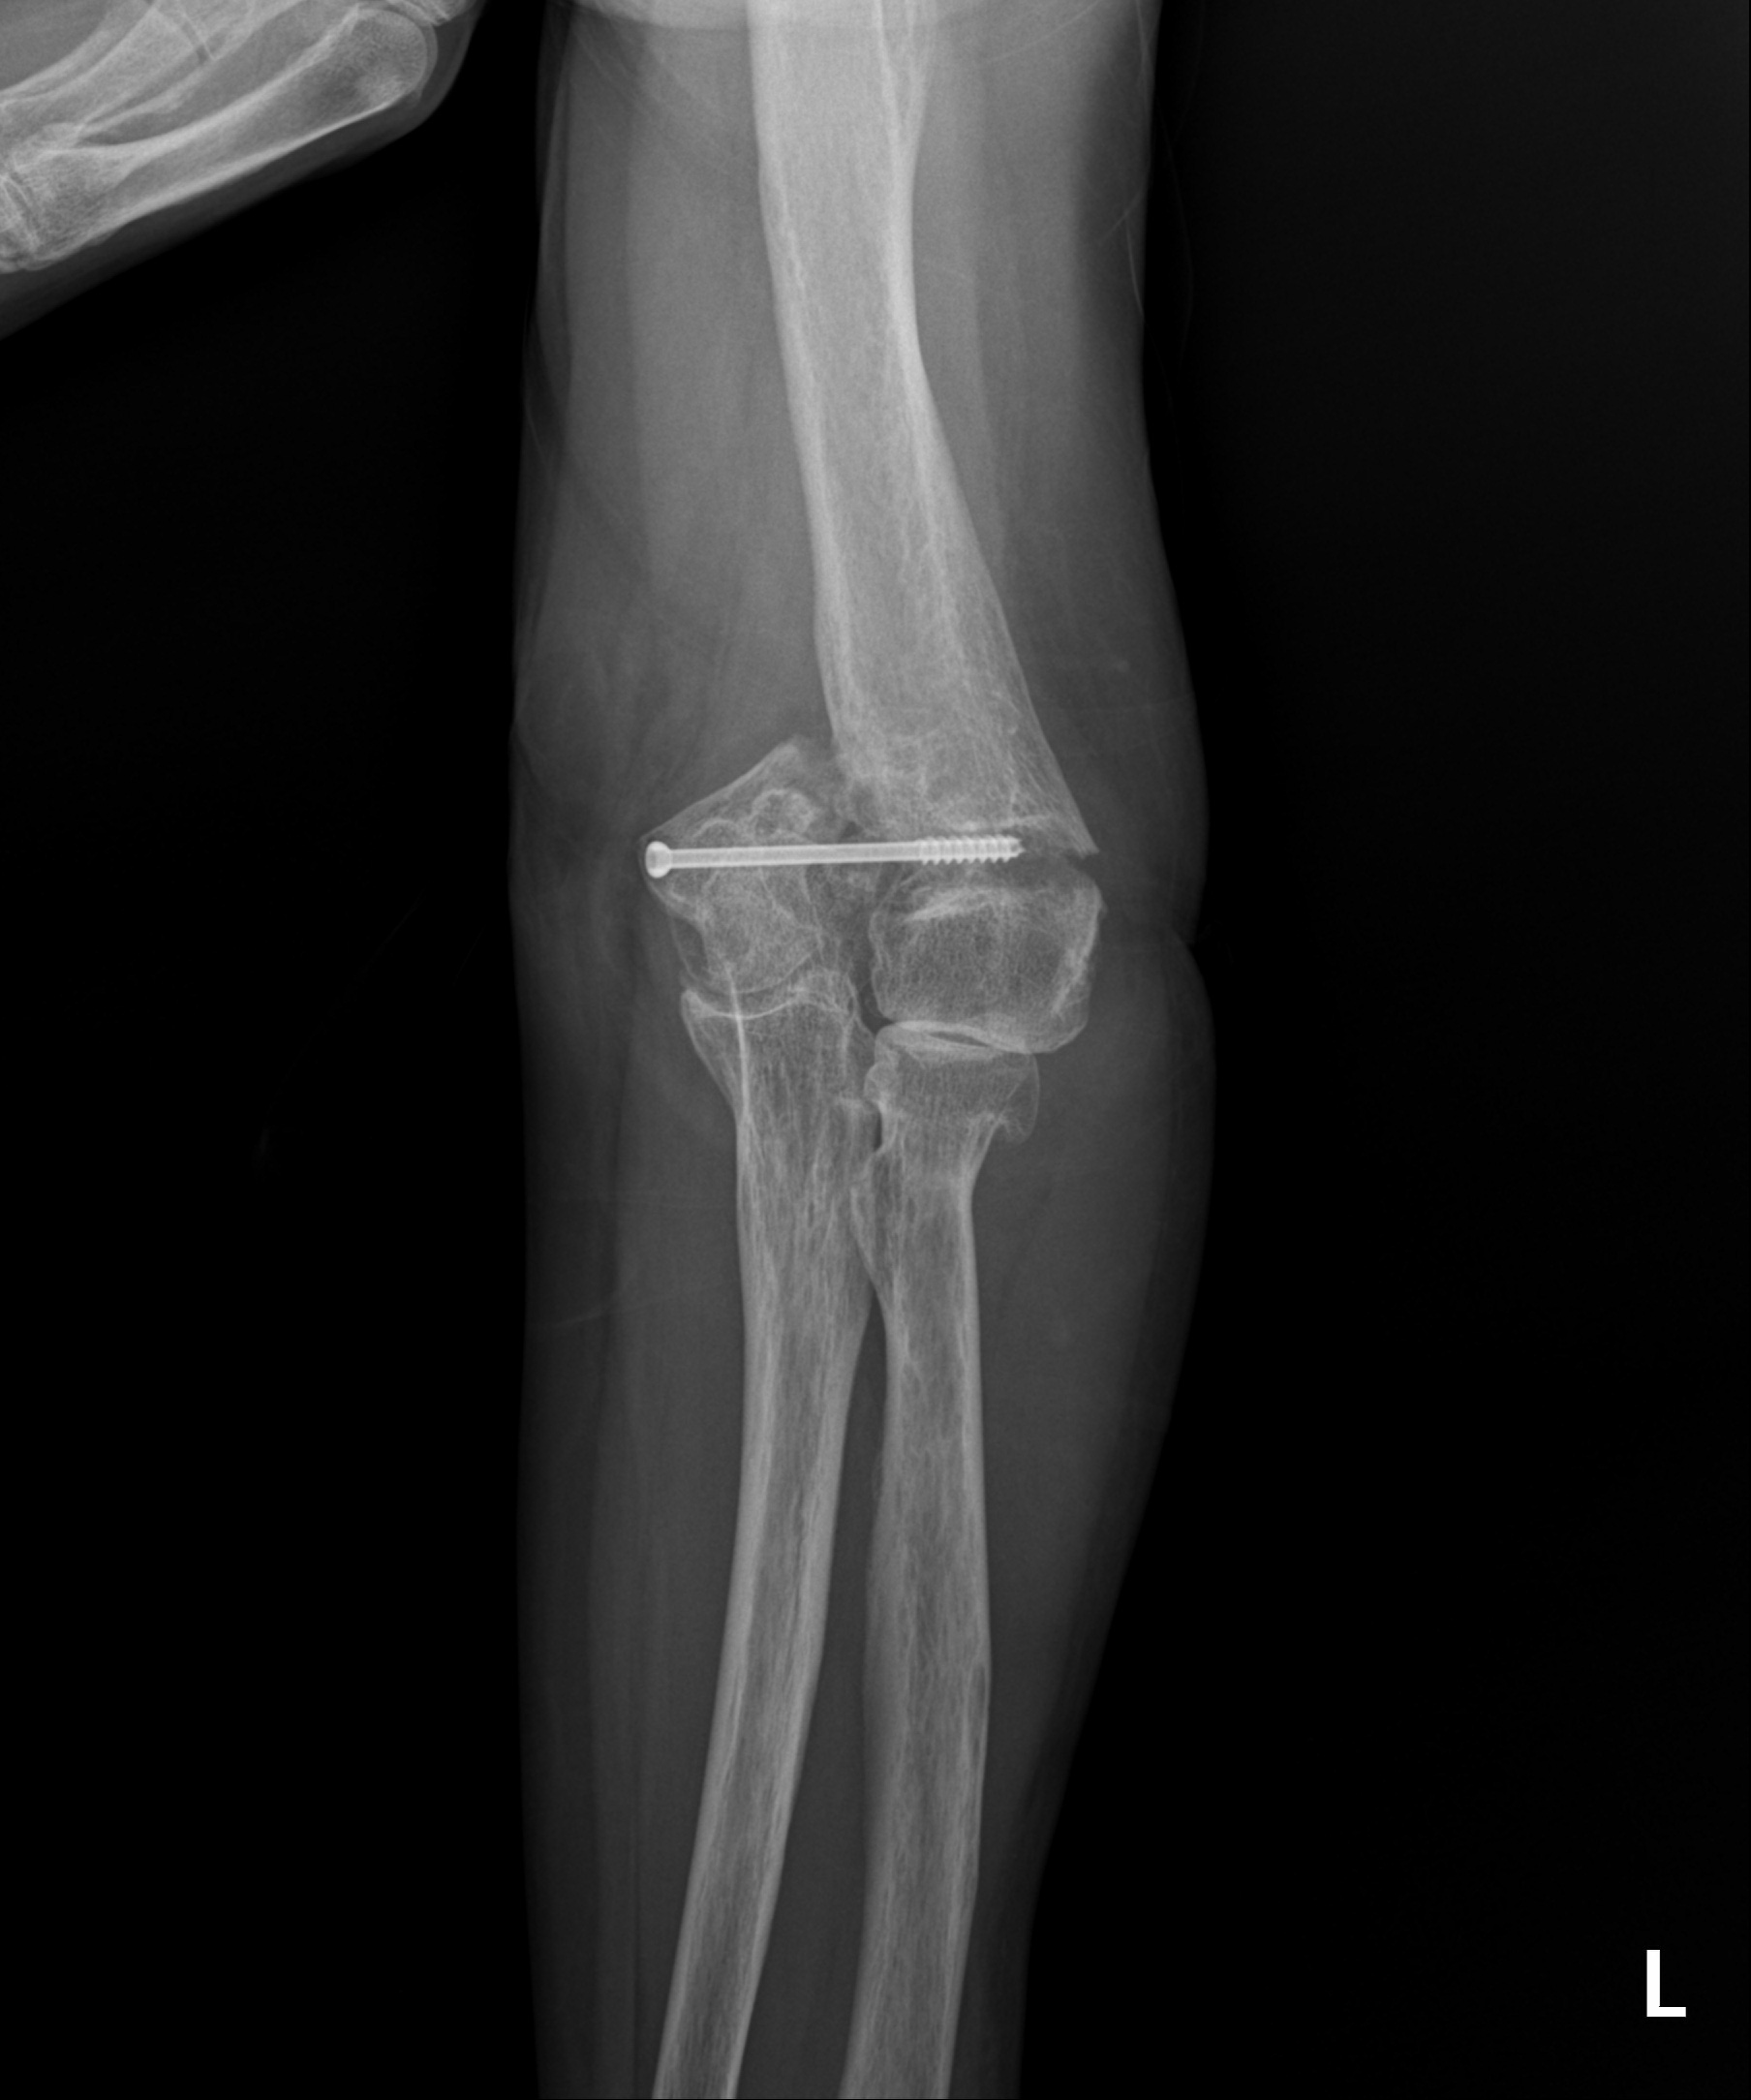

소아 골절

2023.02.09

2023.03.29

2023.02.14

2023.02.16